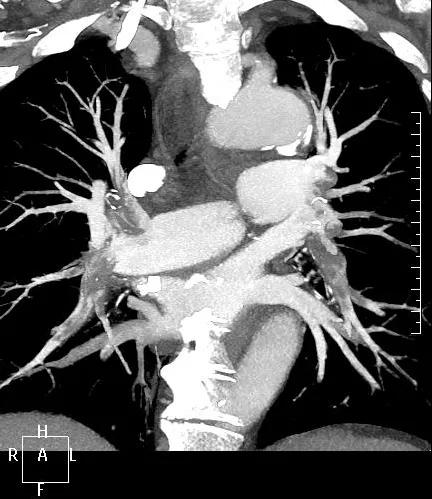

近日,一名港胞翁阿姨在我市突發(fā)急性肺栓塞,生命垂危。市二院在接到120出車(chē)指令后,迅速響應(yīng),患者入院后開(kāi)通綠色通道,經(jīng)急診科、心內(nèi)科、介入科、重癥醫(yī)學(xué)科等多學(xué)科專家開(kāi)展聯(lián)合會(huì)診,并于當(dāng)晚9點(diǎn)行“下腔靜脈、肺動(dòng)脈造影+導(dǎo)管溶栓+濾器植入術(shù)”,患者終于轉(zhuǎn)危為安,經(jīng)后續(xù)治療與精心護(hù)理,病情逐漸穩(wěn)定,現(xiàn)已轉(zhuǎn)入普通病房。